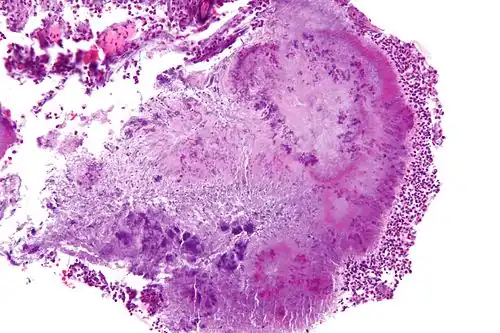

Actinomyces is a genus of the Actinomycetia class of bacteria. They all are Gram-positive and facultatively anaerobic, growing best under anaerobic conditions.[2] While individual bacteria are rod-shaped, Actinomyces colonies form fungus-like branched networks of hyphae.[3] The aspect of these colonies initially led to the incorrect assumption that the organism was a fungus and to the name Actinomyces, "ray fungus" (from Greek actis, ray or beam, and mykes, fungus).

Actinomycota are normally present in the gingiva, and are the most common cause of infection in dental procedures and oral abscesses. Many Actinomyces species are opportunistic pathogens of humans and other mammals, particularly in the oral cavity.[7] In rare cases, these bacteria can cause actinomycosis, a disease characterized by the formation of abscesses in the mouth, lungs, or the gastrointestinal tract.[2] Actinomycosis is most frequently caused by A. israelii, which may also cause endocarditis, though the resulting symptoms may be similar to those resulting from infections by other bacterial species.[8][9]